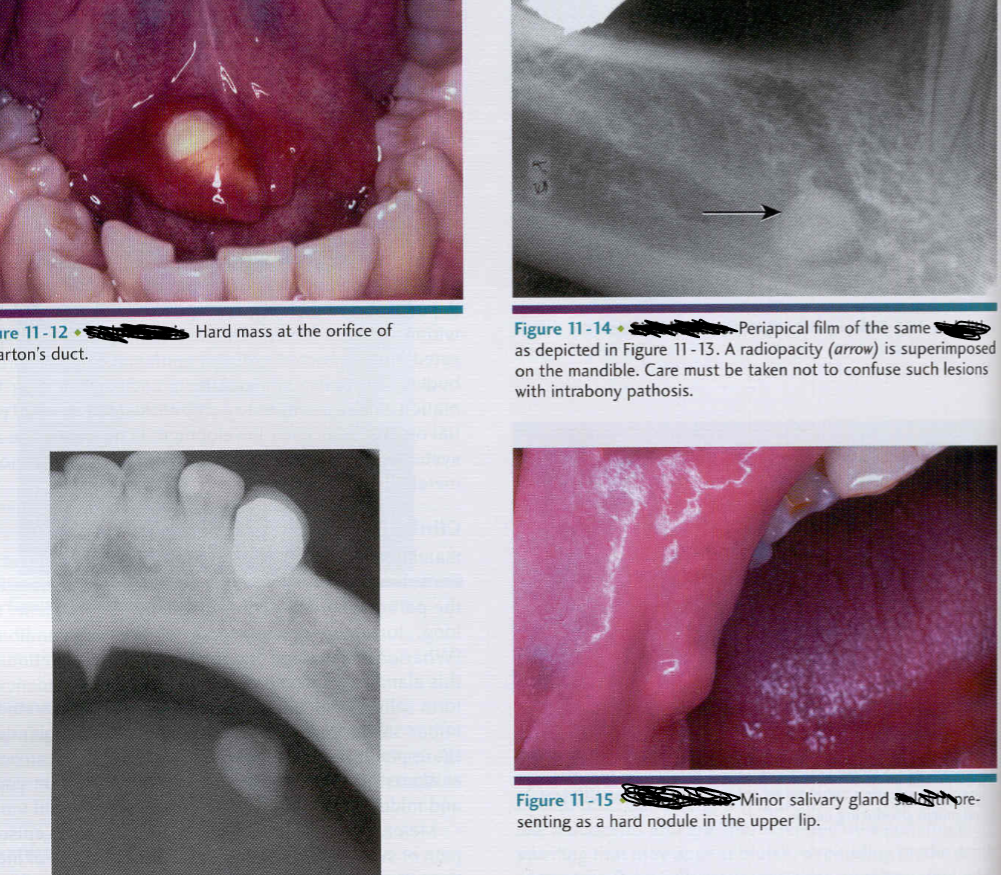

Sialolith